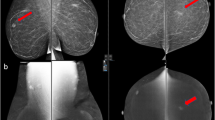

Malignant lesions detected after contrast-directed recall had comparable features to those identified on 2D alone or 2D and C + images in terms of size, grade and nodal status (Table 4). 5/9 (56%) contrast-directed TPs were TNBC or ‘ER-low positive’ (Fig. 2 illustrative case), with two of these patients having ER/PR + HER2- index cancers. Two TPs (2/40, 5%) had no contrast enhancement. One was a small cluster of calcifications with an incidental 1mm invasive lobular carcinoma. The other was clustered calcifications diagnosed as recurrent ipsilateral ER/PR/HER2 + invasive cancer 1 year following BCS and axillary dissection with previous pathological complete response to neoadjuvant systemic therapy. Both patients were on endocrine therapy at the time of recall.

48F Index cancer 2017, 2.8cm TNBC right upper outer quadrant with positive nodes. PET no distant metastases. Treated with NACT with incomplete response. WLE clear margins, 2cm G3 TNBC, 2/29 positive nodes. Adjuvant radiotherapy. 3 surveillance rounds including first CEM 2020, clear. MD BIRADS B. New 19mm NME (white arrow) 2021 anterior to scar, seen on contrast only (2D/3D MG and US normal). MR biopsy 20mm TNBC G3 with LVI. Right Mastectomy

There was a significant difference in contrast-directed recall rate based on breast density (Table 7). 528/1190 (46%) of women in this cohort had density C or D breasts. 12/17 (71%) of contrast-directed TP recalls were in women with density C or D breasts, compared with 5/17 (29%) in the 662/1190 (54%) of women with density A or B breasts (p < 0.001). 21/38 (55%) of contrast-directed FP recalls were in women with density C or D breasts, compared with 17/38 (45%) of women with density A or B breasts (P = 0.006).